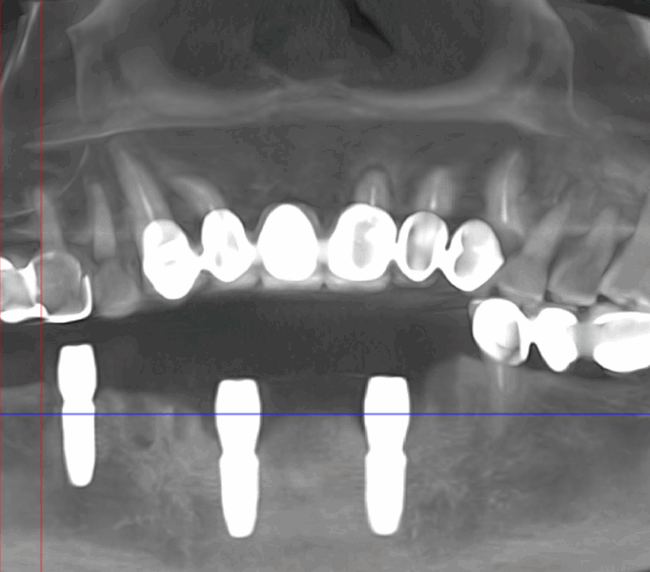

Tomografie (CBCT)

Caz 1